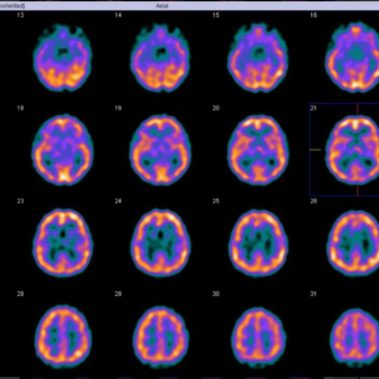

Cenedyt Servicio de Medicina Nuclear se creó hace más de 20 años. Las técnicas de imagen han tenido un desarrollo espectacular en los últimos años y cada vez juegan un papel más relevante en el proceso diagnóstico y terapéutico de los pacientes. El número de exploraciones realizadas es cada vez más elevado.

Estamos especializados en Medicina Nuclear y Densitometría. Nuestro objetivo y ofrecer al paciente la máxima calidad en Diagnóstico y tratamiento, basándonos en nuestra amplia experiencia y últimas tecnologías.